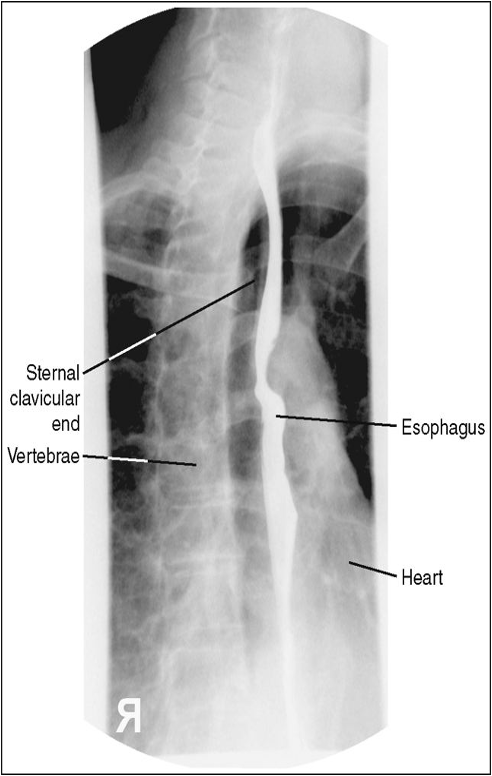

AP/PA Esophagus (CR and Positioning)

Patient supine or prone with arms above head

Center the MSP to the grid

Turn head slightly, to assist drinking the barium

Shield Patient

Place IR at the top of the mouth

CR around T5-T6

Instruct patient to take big swallows and expose while esophagus is full of barium

AP or PA Esophagram Eval Criteria

No rotation of patient

Visualize esophagus through the superimposed thoracic vertabrae

PA Esophagus with Proper positioning

PA Esophagus with Left shoulder rolled up